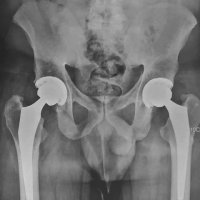

مفصل مصنوعی لگن

مفصل مصنوعی لگن چند سال کار میکنه

علت های شکستگی های اطراف مفصل مصنوعی لگن و ران چیست و چگونه درمان میشود

نحوه کارگذاری پروتز هیپ(مفصل مصنوعی لگن) با سیمان ارتوپدی

توتال هیپ چیست

مثال هایی از جراحی تعویض مفصل ران

ساختمان یک مفصل مصنوعی ران چیست